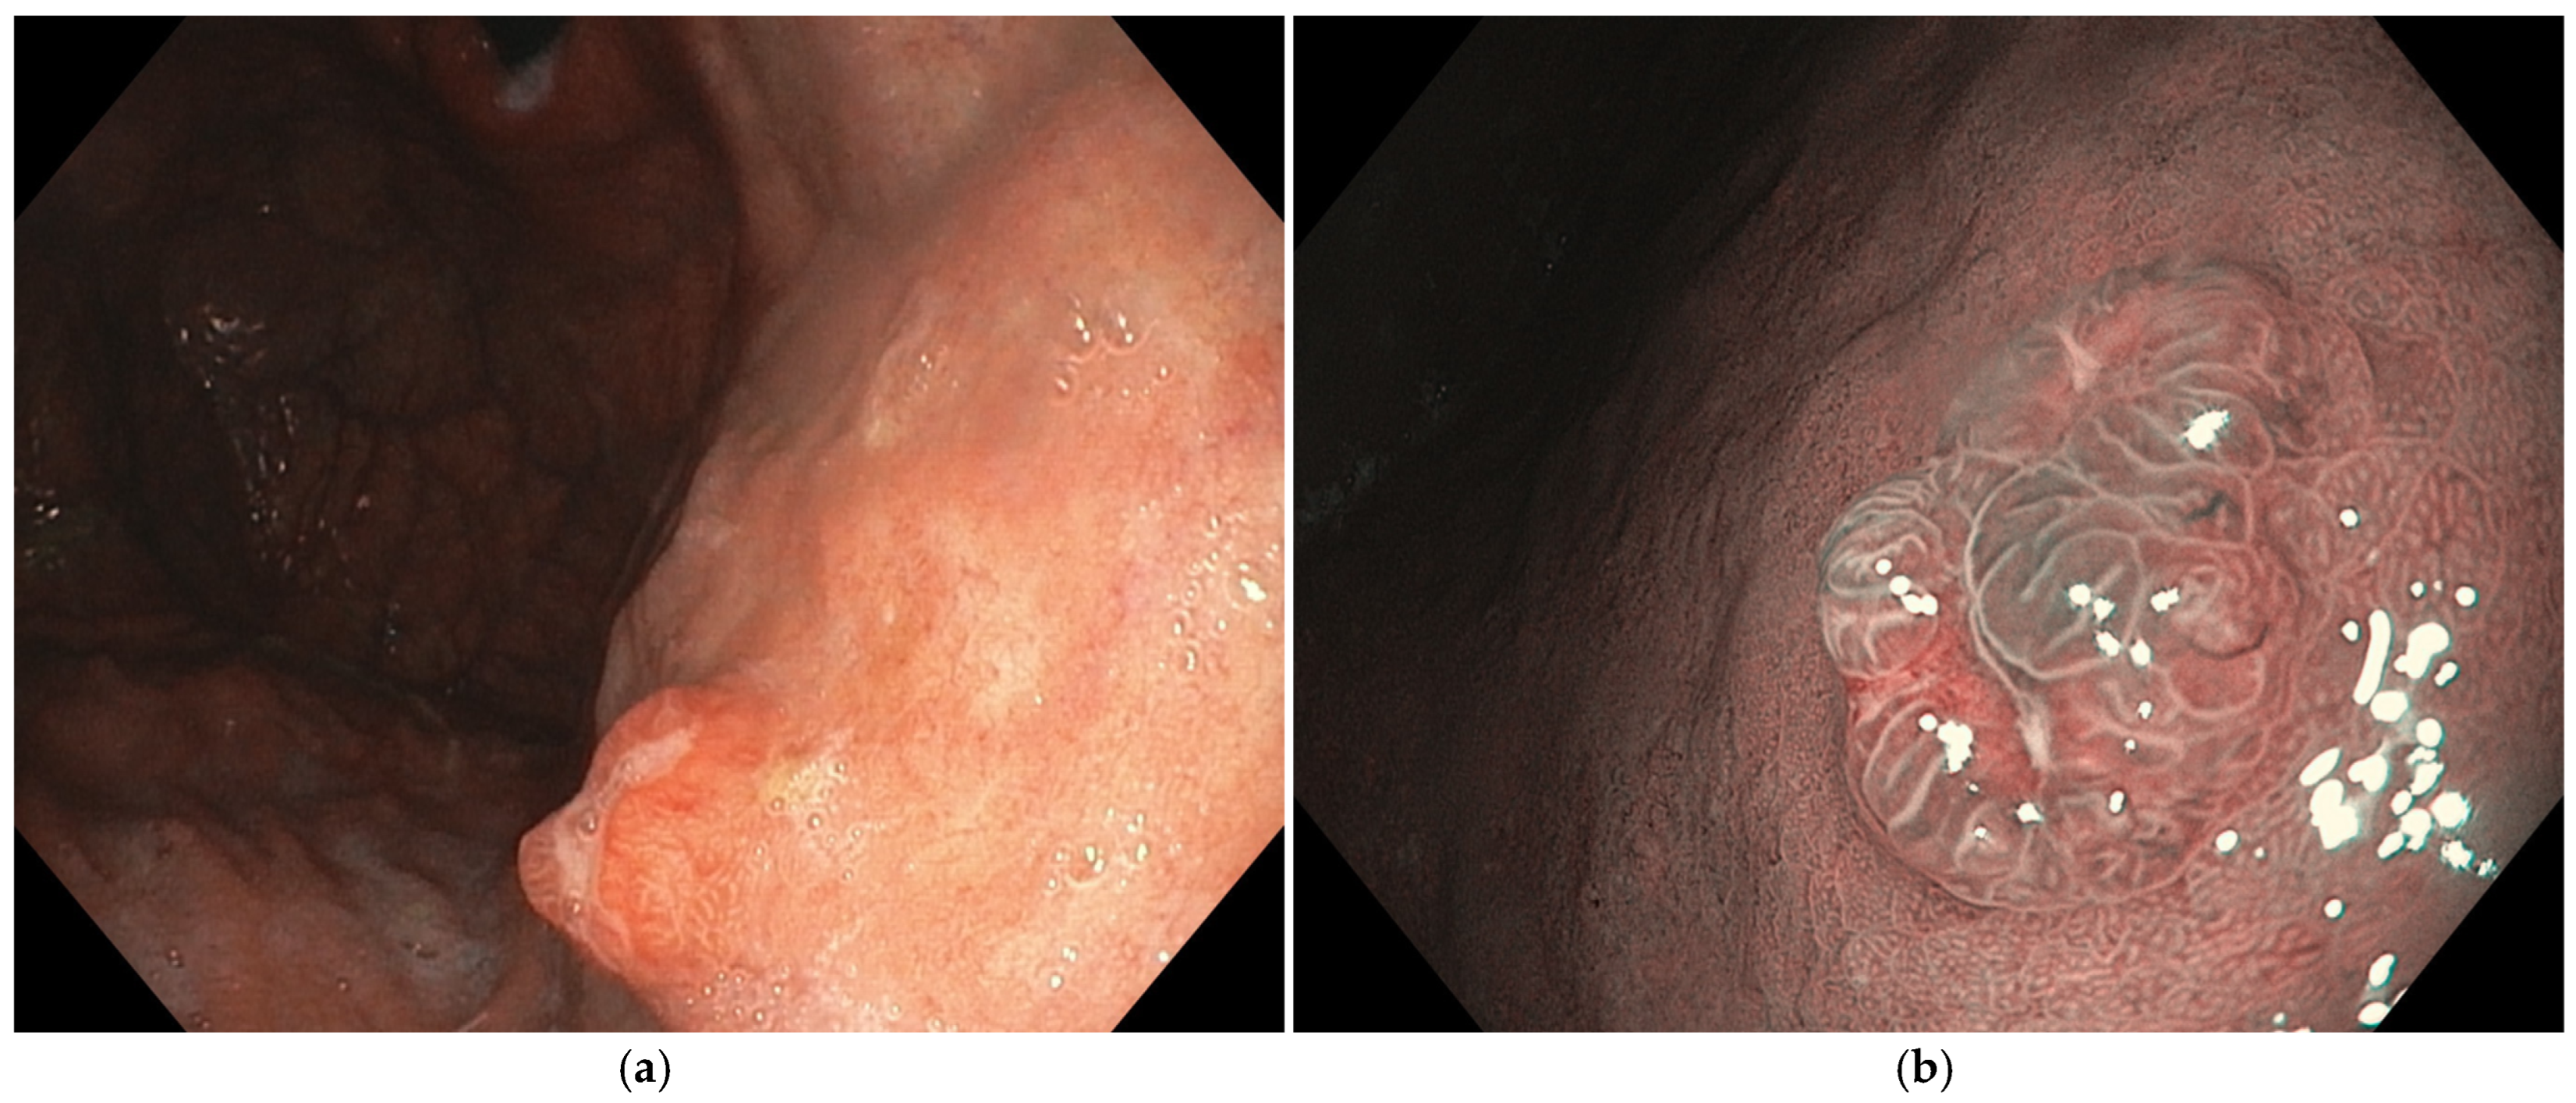

Figure 1. Fundic gland polyps (FGPs). (a) FGPs appear under white light endoscopy as small, smooth, sessile, pale, or translucent dome-shaped elevations, typically less than 5 mm in diameter; (b) FGPs evaluated with enhanced endoscopic image with narrow-band imaging (NBI) exhibit a distinctive whitish color against the darker background, featuring a characteristic “starfish” or “snowflake” surface pattern; (c) histopathologic features of FGPs, cystically dilated fundic glands aligned with parietal cells. Images were provided by Dr. Glòria Fernández-Esparrach (a,b) and Dr. Iván Arcilla (c).

FGPs are usually smaller than 10 mm, sessile (Paris 0-Is) or semi-sessile, hyperemic or with a similar color to the normal mucosa, translucent with a smooth and shining surface, and have small blood vessels visible on the surface and a round dotted surface pattern. The mucosa surrounding the polyp usually is normal, and they are commonly located in the gastric fundus and body [2,14,27].

The sporadic FGPs are mainly derived from oxyntic glands and are characterized by cystically dilated fundic glands aligned with parietal cells, chief cells, or foveolar/mucosal neck cells (Figure 1) [20].